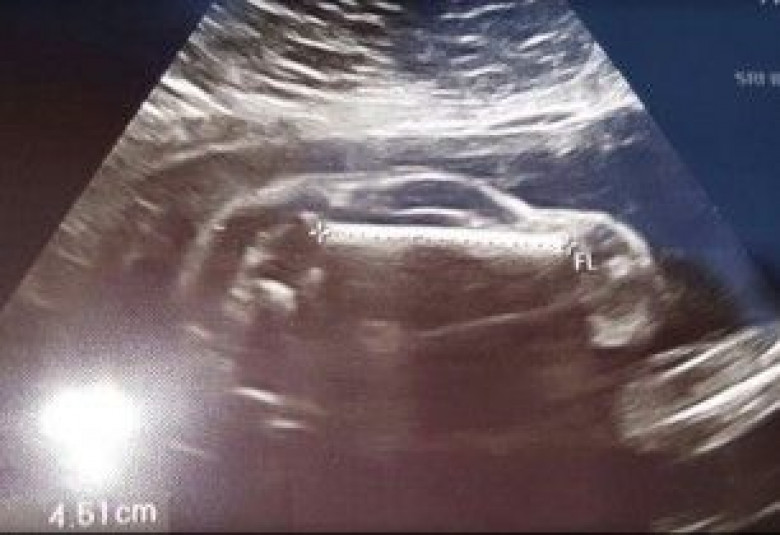

Սոնոգրաֆիան ցույց է տվել ... զույգը երեխա-մեքենայի է սպասում

Միսսուրիում բնակվող հղի զույգը, որը գնացել է սոնոգրաֆիա անելու և տեսնելու, թե ինչ սեռի երեխայի են սպասում, պատմել են, որ էկրանին նրանց տեսած պատկերը նման չի եղել ոչ տղայի, ոչ աղջկա, գրում է CBS News-ը:

Հպարտ ապագա հայրը՝ Մայք Ռոբերթսը, Reddit կայքում հայտարարել է. «Կինս հղի է սպորտային մեքենայով»:

Ռոբերտի կարծիքով երեխան Bugatti է՝ աշխարհի ամենաթանկարժեք, շքեղ սպորտային մեքենաներից: